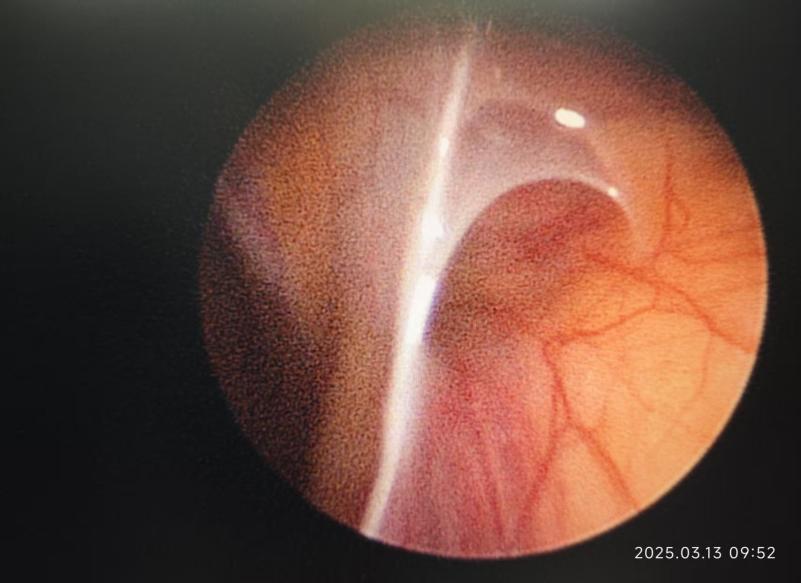

手术过程中的情况

2mm腹腔镜下双侧内环口未闭的情况